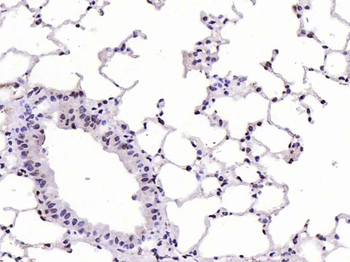

CDKN1A Antibody

Catalog Number: orb682382

| Catalog Number | orb682382 |

|---|---|

| Category | Antibodies |

| Description | CDKN1A Antibody |

| Species/Host | Rabbit |

| Clonality | Polyclonal |

| Tested applications | ELISA, WB |

| Reactivity | Human, Mouse, Rat |

| Isotype | IgG |

| Immunogen | Human P21 |

| Form/Appearance | Liquid |

| Conjugation | Unconjugated |

| Target | CDKN1A |

| UniProt ID | P38936 |

| Storage | Maintain refrigerated at 2-8°C for up to 2 weeks. For long term storage store at -20°C in small aliquots to prevent freeze-thaw cycles. |

| Buffer/Preservatives | PBS with 0.02% Sodium Azide, 50% Glycerol, pH 7.3. -20°C, Avoid freeze / thaw cycles. |

| Alternative names | Anti-cyclin-dependent kinase inhibitor 1A (p21 ant Read more... |

| Note | For research use only |

| Expiration Date | 12 months from date of receipt. |